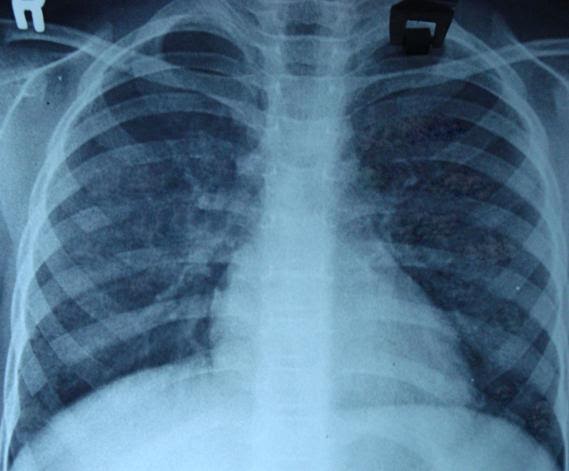

Рентгенологические признаки гемосидероза легких